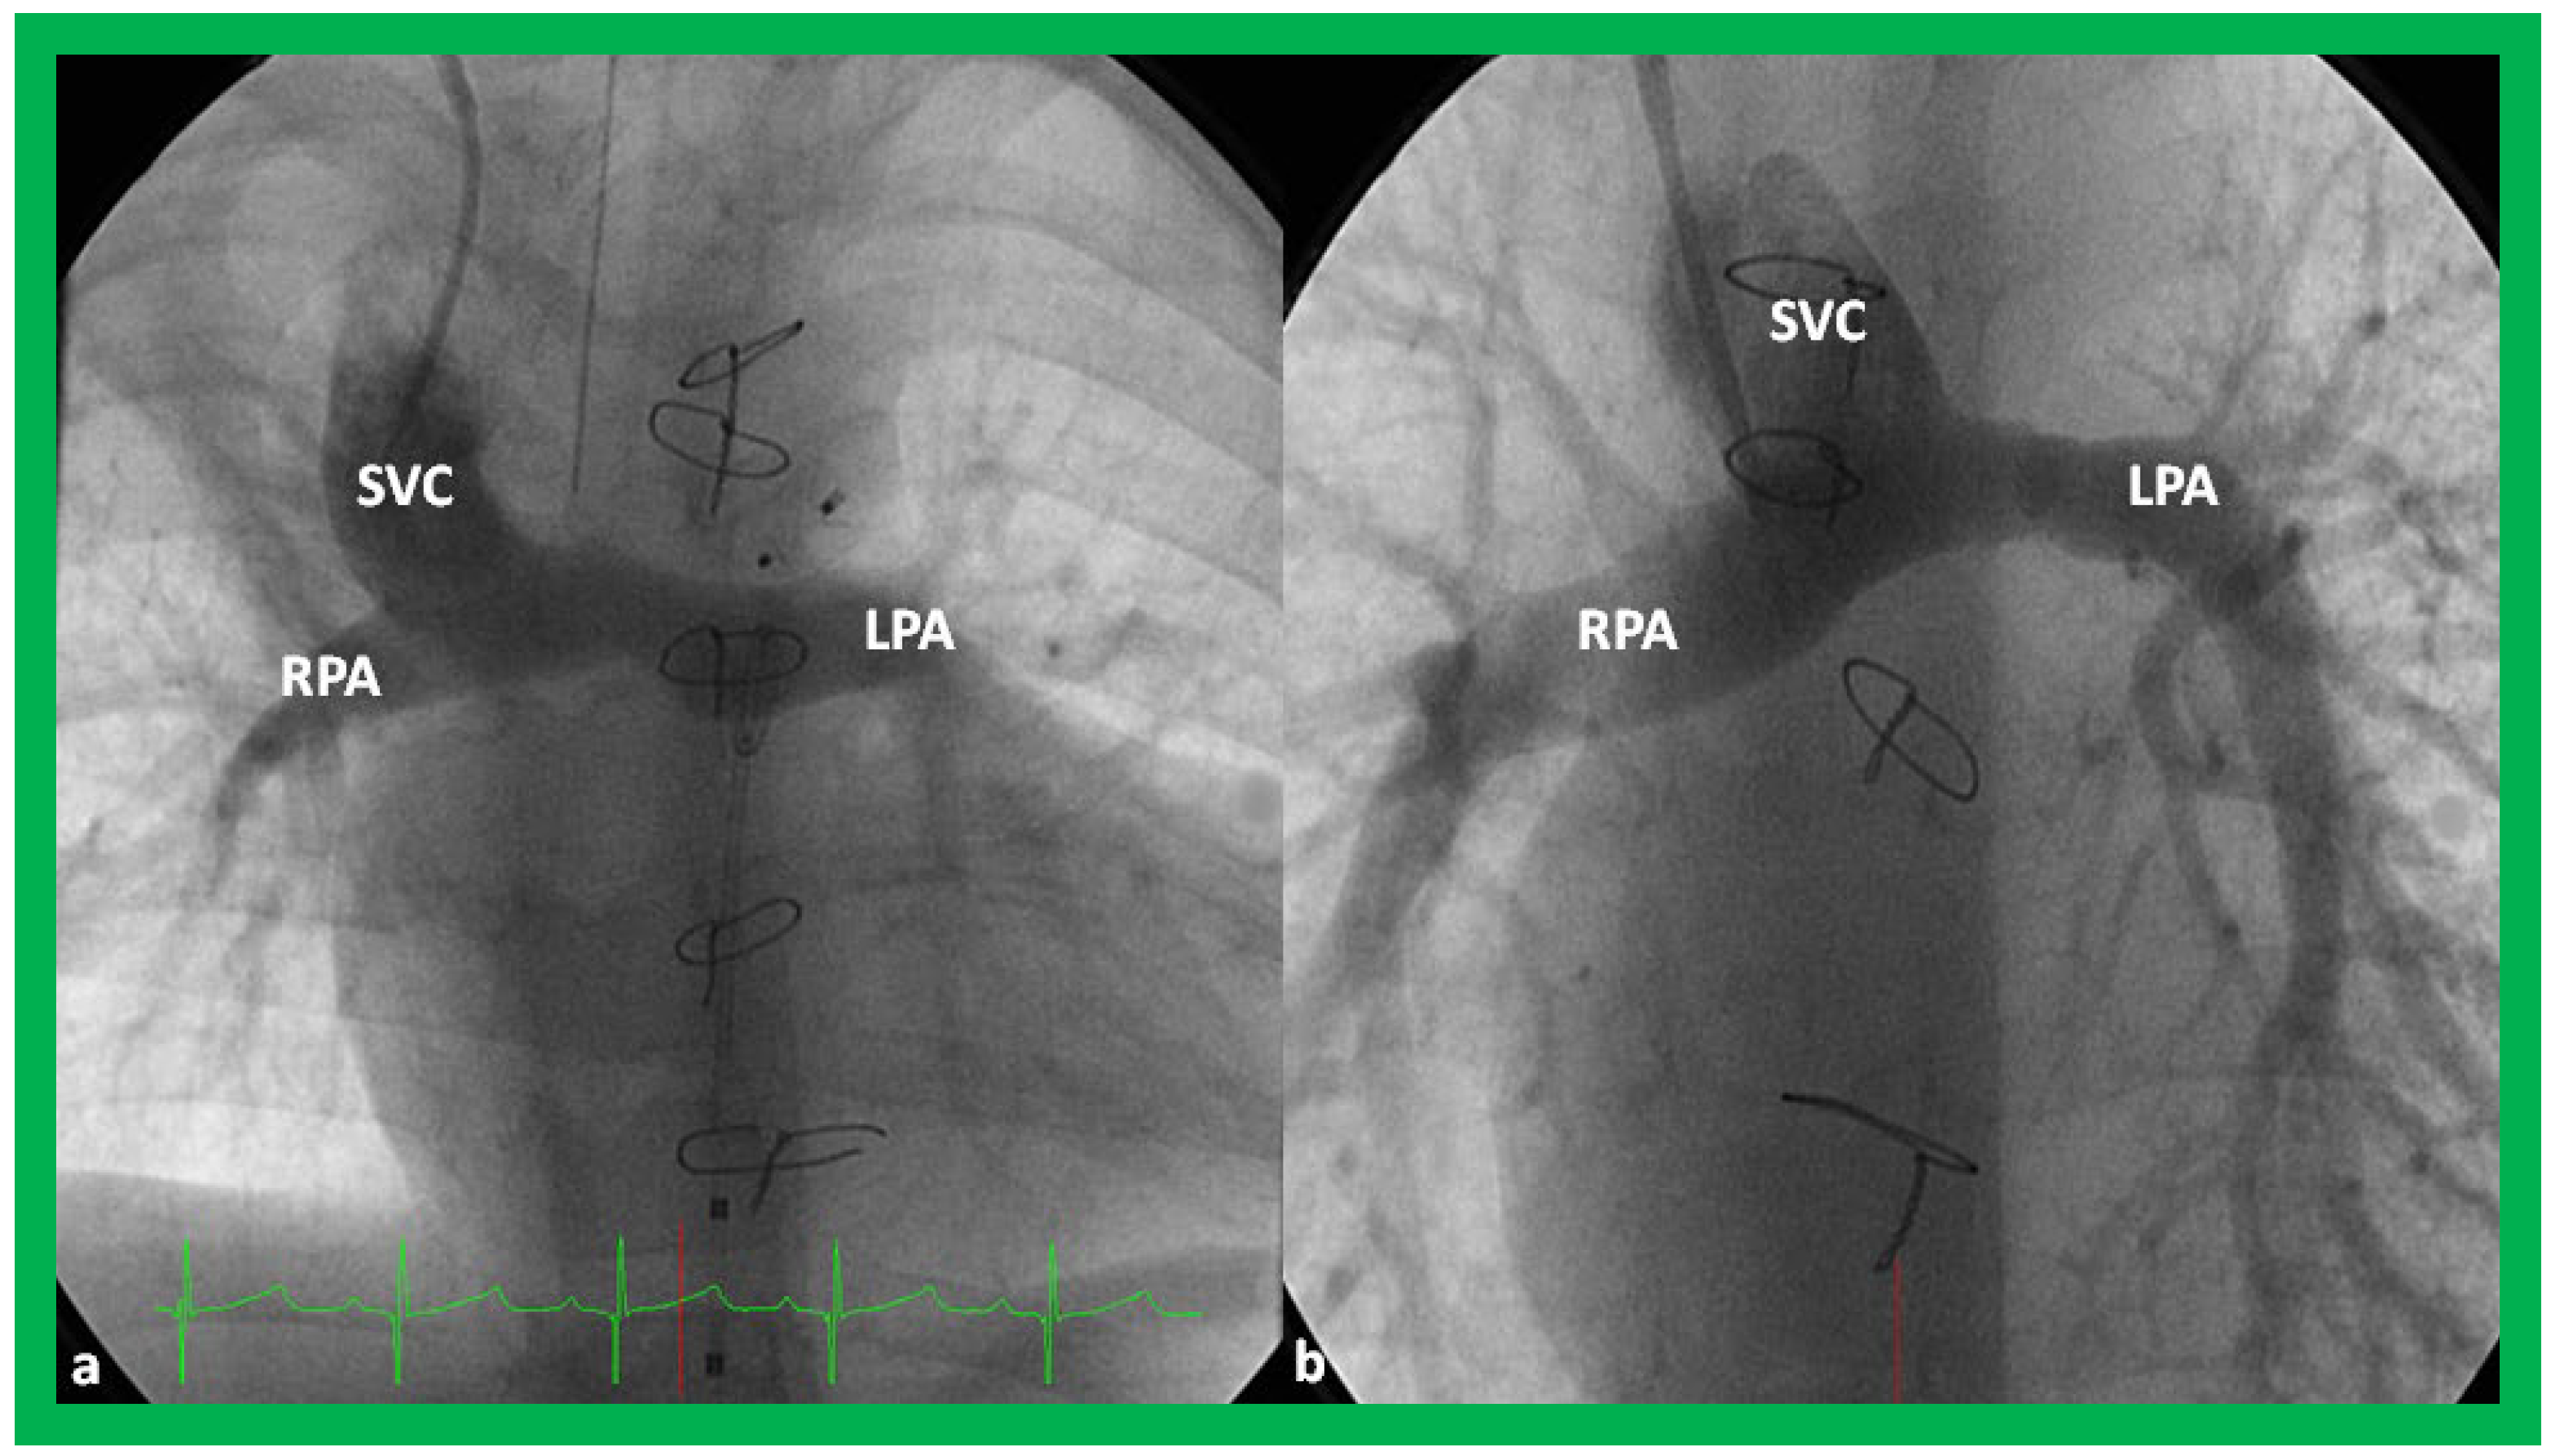

Angiographic counter parts of both the palliative procedures are shown in Figure 24, to have better comprehension of the anatomy of these procedures.

Angiographic counter parts of the bidirectional Glenn are shown, in Figure 29, to have better comprehension of the anatomy of the bidirectional Glenn.

Figure 24. Selected cine frames in postero–anterior (a) and lateral (b) views, demonstrating a Blalock–Taussig (BT) shunt (arrow in a) to care for infants with decreased pulmonary blood flow (a) and pulmonary artery banding (PB) (arrow in (b)) in babies with increased pulmonary blood flow (b), respectively, during Stage I of Fontan procedure. C, catheter; LPA, left pulmonary artery; RPA, right pulmonary artery. Neonates with adequate pulmonary blood flow do not need any intervention and can go directly to Stage II at about the age of 3 months. Reproduced from Rao PS, Indian J Pediatr 2015;82:1147–1156 [36].

Figure 29. Selected cine frames in postero–anterior (a) and sitting up (b) views, demonstrating bidirectional Glenn procedure (the superior vena cava [SVC] is anastomosed with the right pulmonary artery [RPA]) in two different patients during Stage II of Fontan procedure. Unobstructed flow from the SVC to the right (RPA) and left (LPA) pulmonary arteries is shown. Reproduced from Rao PS, Indian J Pediatr 2015; 82:1147–1156 [36].